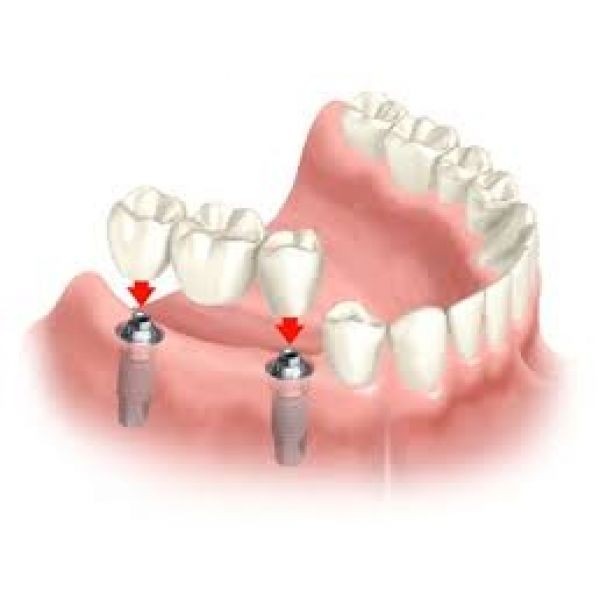

Implante dentário é formado por um cilindro (pino) de titânio, que é inserido dentro do osso, abaixo da gengiva. O tamanho do cilindro varia entre 3 e 6 mm de diâmetro. O titânio, metal biologicamente compatível que se integra perfeitamente ao osso, tem a peculiaridade de impedir qualquer tipo de rejeição óssea. Dessa forma, o implante dentário faz o papel da raiz do dente. Sobre os implantes é que são colocadas as próteses em metalocerâmica, que é o material mais semelhante ao dente natural.